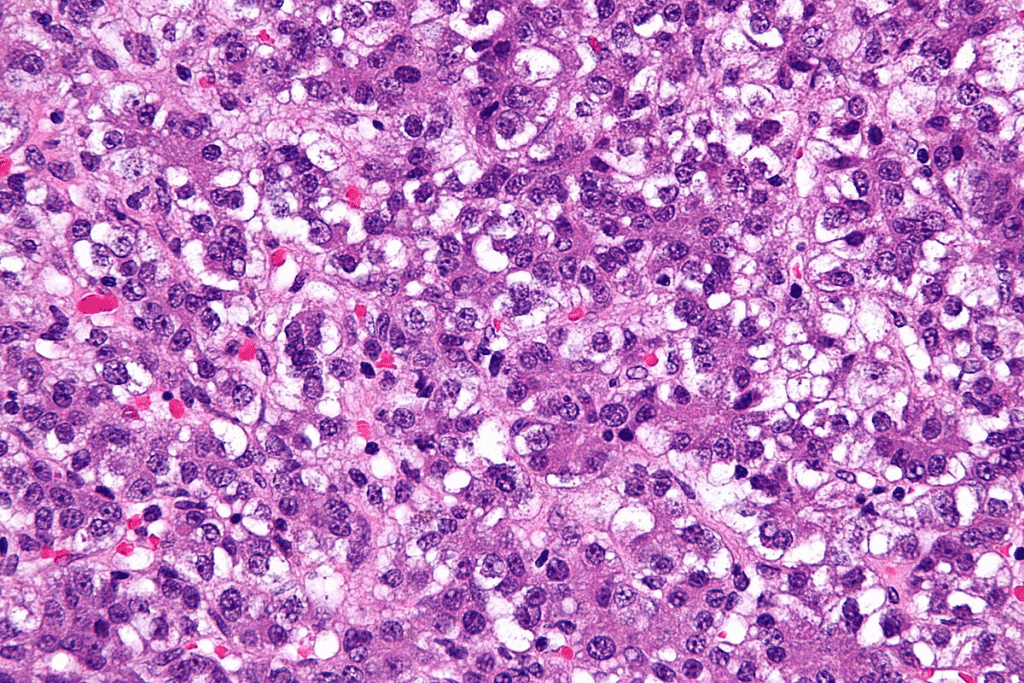

Biopsy is the best way to confirm liver tumor diagnosis, by looking at tissue samples. There are many biopsy methods, like needle, laparoscopic, and surgical biopsies. The choice depends on the tumor’s location, size, and the patient’s health.

Biopsy techniques are chosen to get enough tissue for diagnosis safely. The tissue exam confirms the diagnosis and helps decide the best treatment.